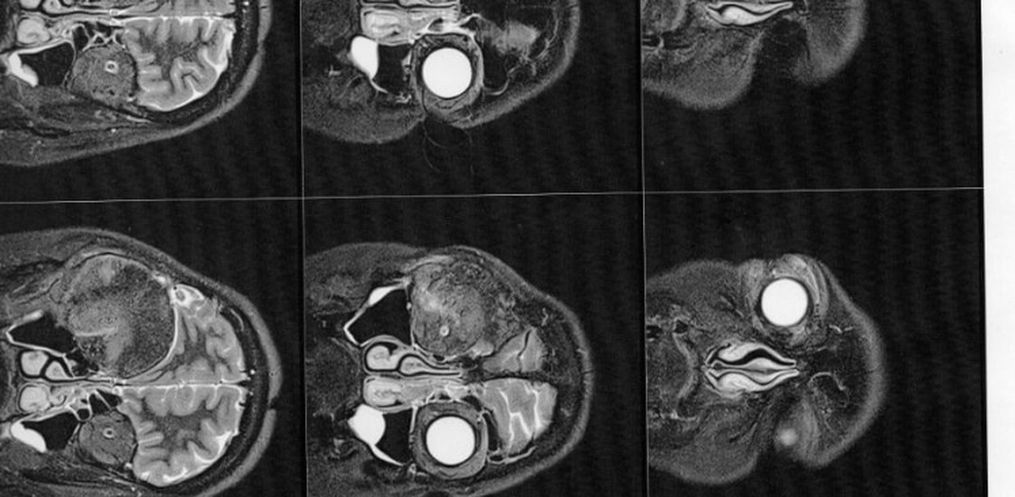

1 ano e 7 meses após o nascimento da Manuela (hoje com quase 4 anos), mais precisamente em dezembro de 2018, Gisele foi em busca de um neurocirurgião que estivesse apto a realizar a cirurgia. Optou-se por um médico da região, pela facilidade de locomoção. Por sua vez, por meio de exames de imagem, este médico a diagnosticou com um meningioma intraósseo (tumor cerebral benigno que se origina nas células das meninges).

Em fevereiro de 2019 passou pela primeira cirurgia de retirada do meningioma. Tudo correu bem, sem sequelas. No entanto, teve uma parte do osso (medindo 7,5 x 6 x 2 cm) em sua cabeça que teve que ser retirado e não pôde ser colocado novamente, pois o tumor estava enraizado naquela região, e eram grandes as chances de reincidência. Após a cirurgia, foi enviado para análise a amostra do tumor, que confirmou, de fato, se tratar de um tumor benigno.

Então este médico solicitou exames de imagem (ressonância magnética e tomografia) para avaliar a situação, os quais foi constatado que o meningioma ainda está ali, e que continua empurrando o olho e se expandindo para outras áreas. Trata-se de um meningioma gigante (medindo 6 x 6,6 x 6 cm), que está localizado na placa do assoalho da fossa média e anterior.